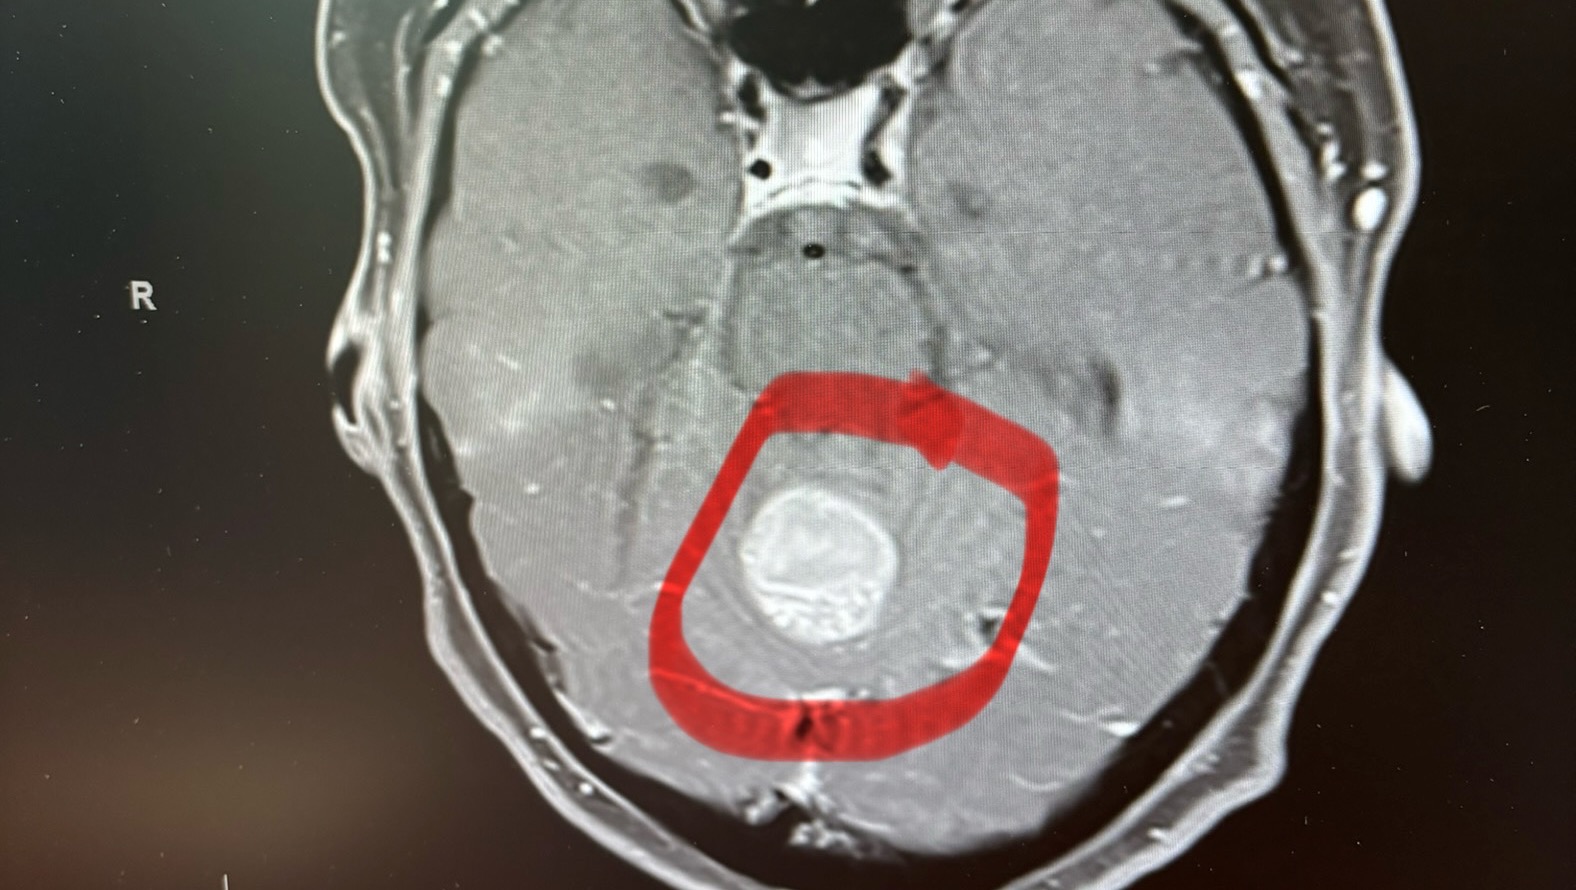

Unfortunately, on April 29th of this year she was rushed to the ER due to dizziness, pain, and nausea, and then results revealed what any cancer survivor fears most: after MRIs, it was shown that the cancer had spread to her brain. She had emergency brain surgery on May 1st 2024 and has since been recovering and seeking complimentary treatments alongside the BC Cancer Agency. If you are able to help contribute, please know that a little goes a long way. Contributions to this go-fund me will go directly to her DCA (Dichloroacetate) treatments, IVC, and B12 injections.